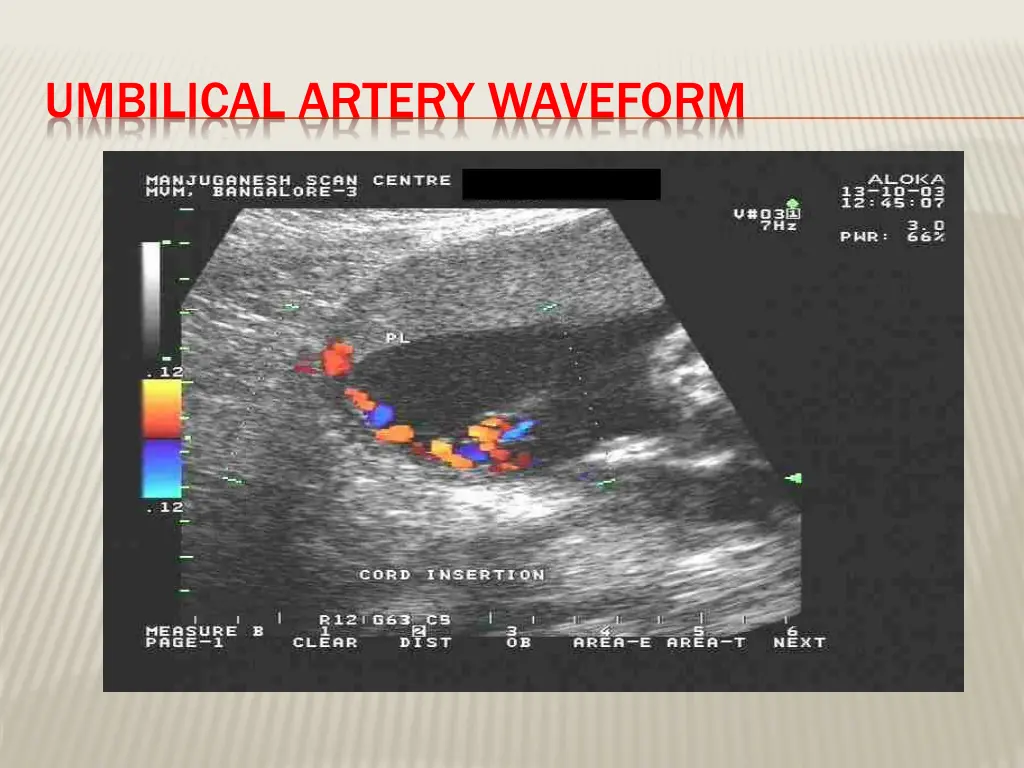

DOPPLER VELOCIMETRY Measurement of blood flow velocities in maternal & fetal vessels Reflect feto-placental circulation Doppler indices from UA, Uterine A & MCA Doppler studies is mostly valuable IUGR In IUGR absent or reversed EDF (end diastolic flow) associated with fetal hypoxia